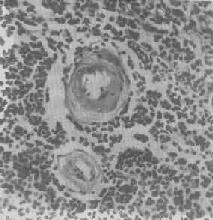

图1-20 脾中央动脉玻璃样变

中央动脉管壁明显增厚,呈玻璃样均质状,管腔变窄